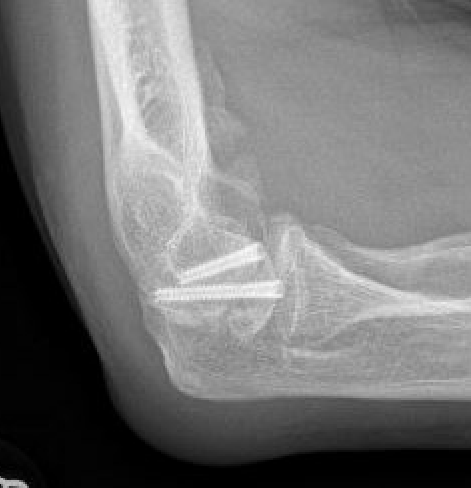

Xray

Elbow HOHOElbow Myositis Ossificans

HOHO

Radio-ulna synostosis

synostosissynostosis